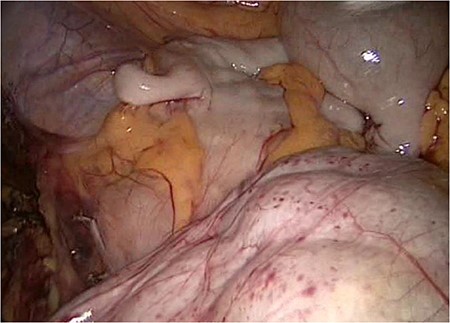

The laparoscopic anterior resection was performed in February 2019. The patient was positioned in a modified lithotomy position. The pneumoperitoneum was established by a Veress needle. The trocars were placed umbilical, two on the left and one on the right abdominal wall. The descending colon and the endoscopic ink-marked region were visualized perfectly. While getting an overview of the abdominal cavity, we noticed an abnormality in the ileum region. It seemed that the peritoneum was covering the entire ileum. The situs is depicted in Figs 1–4.

On the left side, we show the retroperitoneal pancreas, with the (as well) retroperitoneal jejunum on the right side.

The entire small bowel was found retroperitoneal covered by a slim peritoneal layer (Fig. 1). The dorsal peritoneum covering the ileum was opened (Fig. 2).